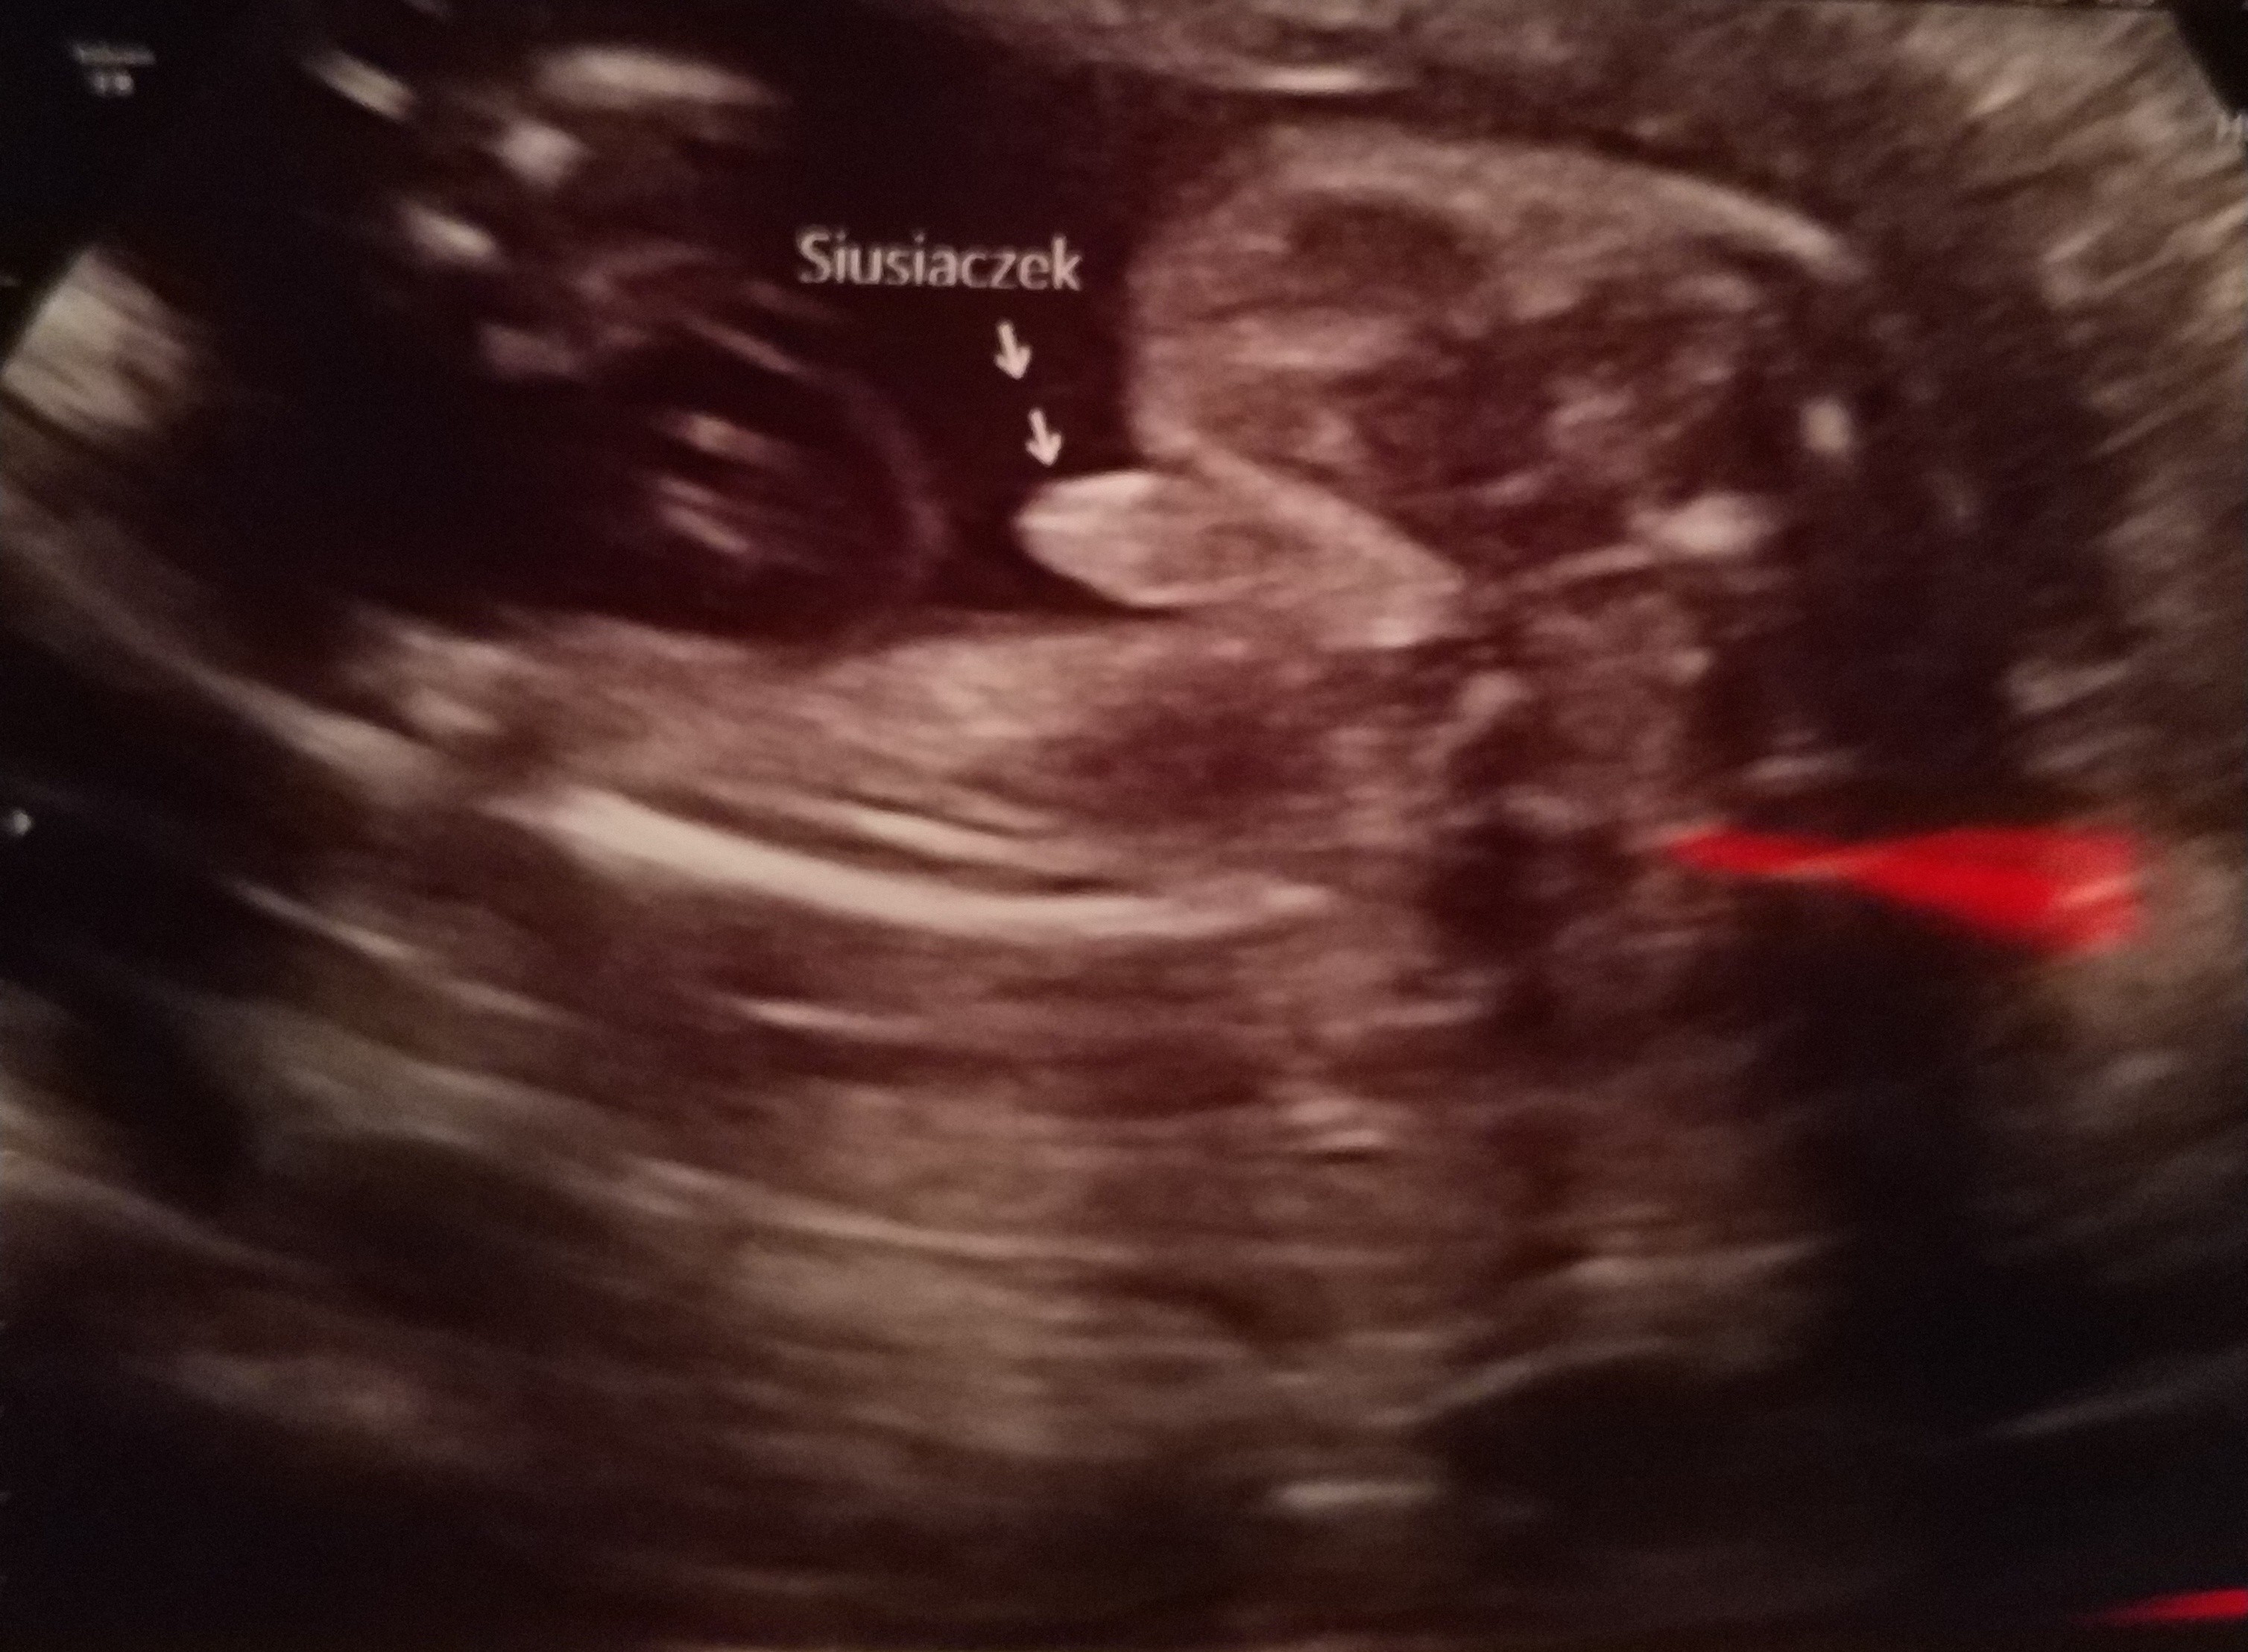

Płeć: chlopiec

• IMG_20181228_220853.jpg

IMG_20181228_220853.jpg

2,2 MB · Wyświetleń: 3 589